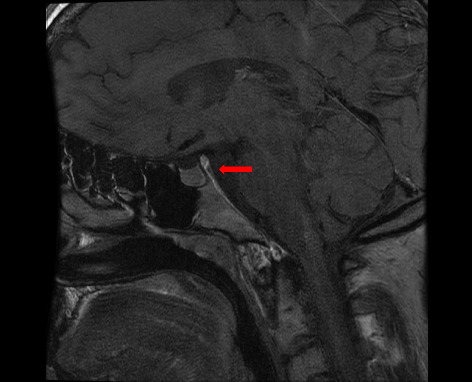

成人朗格汉斯细胞组织细胞增多症(LCH)是一种罕见的疾病。该病表现为局灶性或多灶性累及单一器官/系统或局灶性或弥散性多系统疾病。累及中枢神经系统(CNS)也不常见,尿崩症是垂体后叶病变的常见表现。活检证实诊断为特征性朗格汉斯细胞浸润,免疫组化S100蛋白、CD1a和CD68细胞阳性。患者表现为全身性淋巴结病,在淋巴结活检中被诊断为低风险单系统lch基础的独特病理表现。在疾病期间,记录了中枢神经系统受累,患者接受了不同的顺序治疗方案,实现了8年的完全缓解。在成年LCH患者中,随着淋巴结病和中枢神经系统病变的消失,缓解持续时间延长是一种不寻常的临床观察。

Langerhans cell histiocytosis (LCH) in adults is a rare condition. The disease presents with focal or multifocal involvement of a single organ/system or focal or disseminated multisystem disease. Involvement of the central nervous system (CNS) is also infrequent, with diabetes insipidus as a common manifestation of posterior pituitary lesions. Biopsy-proven diagnosis with the observation of characteristic Langerhans cells infiltrate with positive immunohistochemistry of S100 protein, CD1a, and CD68 cells. The patient presented generalized lymphadenopathy and was diagnosed with low-risk single-system LCH-based distinctive pathological findings in a lymph node biopsy. During the disease, CNS involvement was documented and the patient received different sequential therapeutic schemes, achieving complete remission that has been maintained for 8 years. The prolonged duration of remission with disappearance of lymphadenopathy and CNS lesions in an adult patient with LCH is an unusual clinical observation.